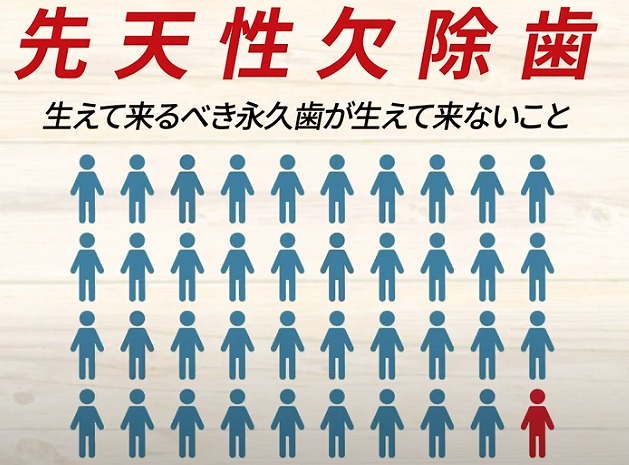

2021.08.27先天性欠除歯(生まれつき歯が生えない)は10人に1人です。

私が小学生の頃は

1学級40人

そしてその中で

1人くらいでした。

ところが現代は

増えてきています。

かつては

30人~40人に一人でしたが

最近の調べでは

10人に1人が歯が足りない

という方が増えています。